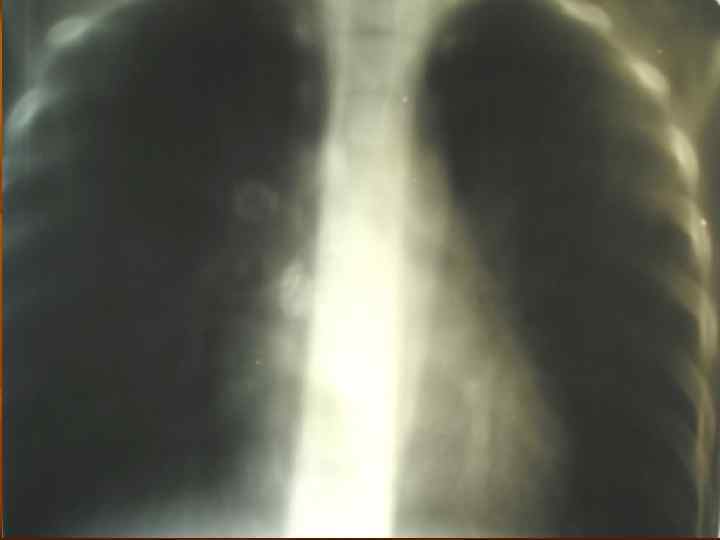

Первичный туберкулезный комплекс n Стадии патологоанатомической (рентгенологической) динамики: пневмоническая, n рассасывания (биполярности), n уплотнения, n кальцинации (формирование очага Гона). n

Первичный туберкулезный комплекс (стадия рассасывания) n Рентгенологическая картина: определяется фокусная тень связанная дорожкой с расширенным корнем (легочный аффект + лимфангоит +лимфоаденит).

Первичный туберкулезный комплекс (стадия организации и уплотнения) n Рентгенологическая картина: определяется плотная очаговая тень в легком и в корне не связанные между собой.

Первичный туберкулезный комплекс (стадия петрификации) n n Вариант клинического излечения Рентгенологически определяется петрификат в легком (очаг Гона) и в корне.